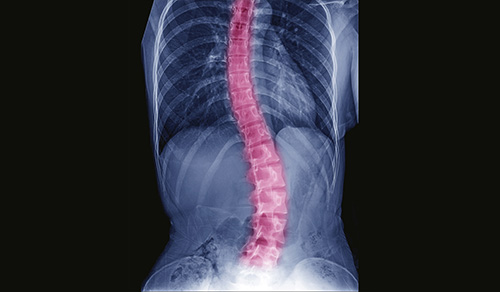

Our pediatric orthopedic specialists from Columbia are among the top in the country, offering specialized expertise in surgical and non-surgical treatments. Renowned for their expertise in congenital, neuromuscular, and traumatic disorders, clinicians and surgeons at the Children's Hospital of New York are also seasoned researchers, seeking to make surgeries safer while optimizing functional and mobility outcomes.

Pediatric Orthopedics